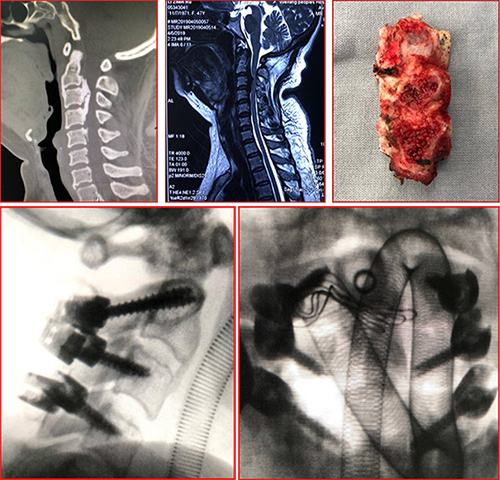

亓女士是一名颈椎后纵韧带骨化症患者,刚接受了颈椎后路减压内固定术,手术顺利,术后麻醉清醒后症状明显减轻。术后查房,精神状态好,四肢活动灵活,手术效果良好。

王大川主任医师团队立刻成立应急小组,并协调院内相关科室多科急会诊。谭炳毅副主任医师一边安抚患者及家属,一边仔细查体,不放过一丝蛛丝马迹。会诊医师建议行颅脑、颈部CT检查,在与CT室协调好后临时为患者开通绿色通道,第一时间行颅脑及颈部CT检查,但结果无异常发现。

患者发病急,症状重,谭炳毅副主任医师根据多年工作经验,建议行颅脑、颈部MR检查,一时间明确诊断的希望寄托到磁共振上。磁共振诊断显示,其颈部切口内血肿压迫了脊髓,造成了四肢软瘫。

“立马手术!”医生作出决定,并马上与手术室、急诊ICU联系协调。手术室与急诊ICU鼎力相助,在10分钟内将亓女士送入了手术室,争取到宝贵的时间,让手术医师第一时间为患者解除压迫,清除血肿。